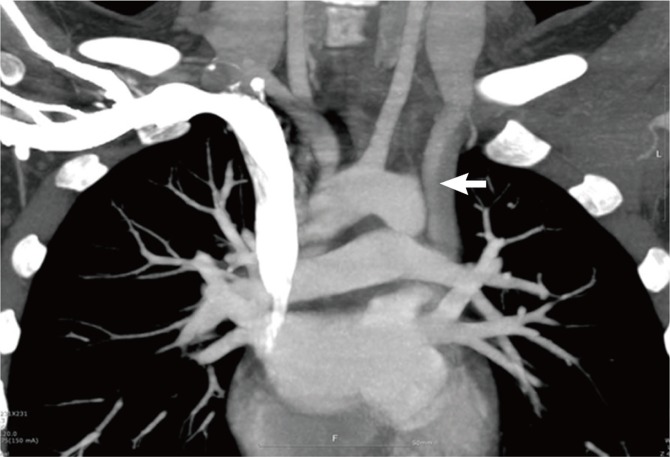

Venous malformations also founded in MDCT. Partial anomalous pulmonary venous return (PAPVR) was the most common (3 patients, 15%, Fig. 3), and the pulmonary veins from the left upper lobe were most commonly connected to the left brachiocephalic vein. Other than these anomalies, 2 patients (10%) had a persistent left superior vena cava (Table 2, Fig. 4).

Fig. 3.

Partial anomalous pulmonary venous return (arrow) from the left upper lobe to the left brachiocephalic vein. There was abnormal venous connection between the left superior pulmonary vein and the left brachiocephalic vein.